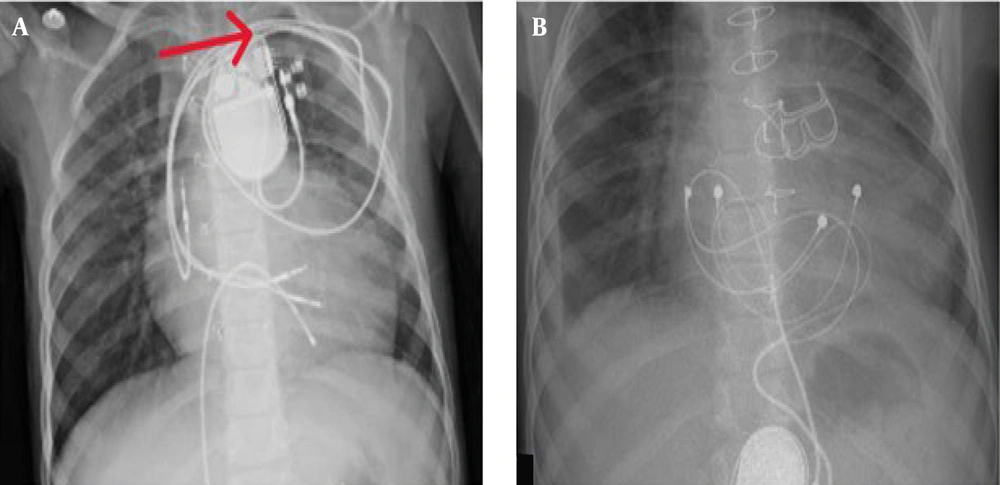

A provisional diagnosis of CIED infection prompted a comprehensive diagnostic workup. Laboratory evaluation revealed leukocytosis with neutrophilia on complete blood count (CBC), and blood cultures grew coagulase-positive S. aureus (Table 1). A chest X-ray showed no evidence of pulmonary complications (Figure 1). Transesophageal echocardiography (TEE) ruled out the presence of vegetation on the device leads or cardiac structures.

Approximately two months after the initial PPM placement, the patient developed localized erythema, swelling, and purulent discharge at the pacemaker pocket in the abdominal region, raising suspicion of a CIED pocket infection. Antimicrobial therapy was initiated, and the infected generator was removed. A new dual-chamber PPM was implanted in the left subclavian region. The patient remained asymptomatic until six months prior to his current presentation, when trauma to the left subclavian region resulted in a fractured ventricular lead. This necessitated the insertion of a new ventricular lead along with two additional leads.

The patient was scheduled for lead extraction. A temporary pacemaker was implanted via femoral vein access to maintain cardiac function during the procedure. The infected ventricular lead was successfully removed, but due to significant adhesions, the remaining two leads could not be extracted transvenously.

To ensure complete eradication of the infection, IV antibiotic therapy was continued for two weeks. Repeat blood cultures after this period were negative for bacterial growth. Subsequently, the patient underwent open-heart surgery to remove the remaining leads. During the procedure, a biological pulmonary valve replacement was performed due to clinical indications. Small lead fragments were intentionally left in the brachiocephalic vein to prevent significant vascular injury.